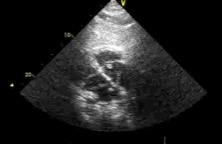

В статье представлен случай успешного хирургического лечения тромбоэмболии легочной артерии у пациентки с высоким риском ранней сердечной смерти на фоне парадоксальной эмболии, осложненной острым нарушением мозгового кровообращения. Криптогенное острое нарушение мозгового кровообращения в комбинации с тяжелой прогрессирующей правожелудочковой недостаточностью на фоне ТЭЛА обусловливает серьезные трудности при принятии решения в отношении тактики лечения у данных больных. Внутрисердечная локализация тромбоэмбола, угрожаемая развитием не только рецидива тромбоэмболии легочной артерии, но и парадоксальной эмболии требует незамедлительного выполнения комплекса дифференциально-диагностического обследования, направленного на верификацию патофизиологического механизма развития заболевания, что во многом определяет эффективность проводимого лечения. Анализ доступных литературных данных, приведенный в работе, а также анализ клинического случая позволяют выработать тактический алгоритм в этой группе пациентов и определить показания к открытому оперативному вмешательству.